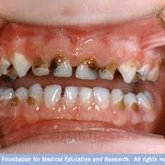

Porcelain crowns and restorations made in one appointment.

We make it a priority to incorporate the latest in dental technology in everything we do at our practice. ...